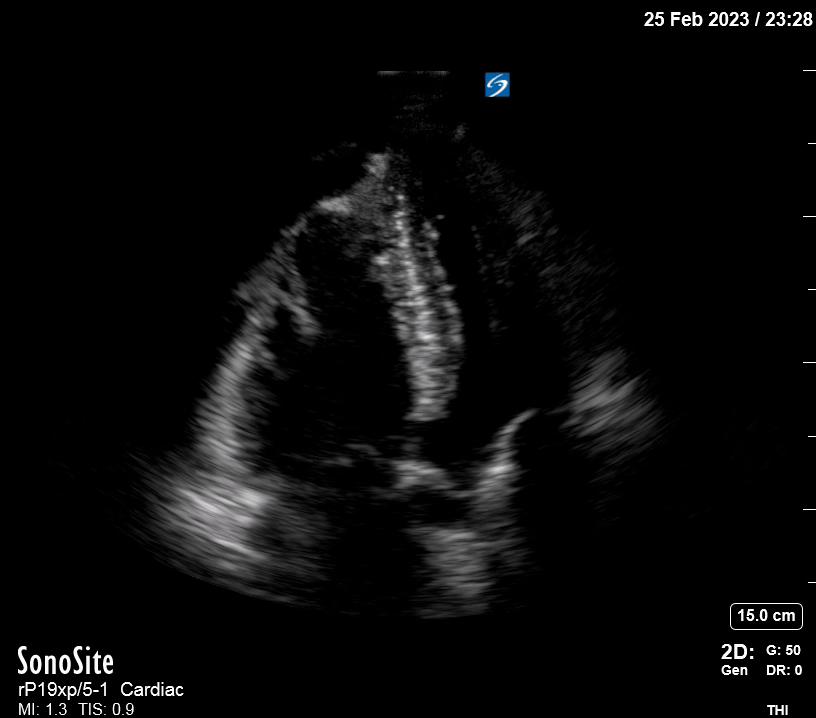

Equality: is the RV dilated or significantly impaired?

Normally, the RV is a low-pressure, thin-walled, high-compliance chamber that wraps anteriorly around the muscular, cone-shaped LV. The normal RV : LV diameter ratio is 0.6 : 1.

When the pulmonary artery pressure rises, the RV will dilate, altering the normal RV:LV ratio. Although sacrificing sensitivity, the use of equality (1:1 ratio) as a cutoff can achieve a specific estimation of RV strain. If imaged correctly by a trained operator, the presence of an RV:LV ratio > 1 is highly specific for RV strain.

RV dilation can be acute, chronic, or acute-on-chronic. However, in patients presenting with undifferentiated chest pain, shortness of breath, hypotension or syncope, the presence of any RV dilation should raise suspicion for acute pulmonary embolism (PE). Furthermore, in a patient in shock, the presence of RV strain may signal the need for aggressive therapy – emergency thrombolysis.

THE VIEWS

The A4C view provides an accurate chamber size comparison. However, achieving a proper A4C view (avoiding foreshortening or ballooning, and visualising the four chambers with a vertically oriented interventricular septum) can be a challenging exercise of image acquisition. Additionally, the PSAX view at the level of the papillary muscles shows both LV and RV side by side and is useful to assess function and size. When RV pressure is high, the septum will be pushed and flattened towards the LV, resulting in the characteristic “D-shaped” LV or “D sign”.

PITFALLS

When comparing size, beware of correct image acquisition, as oblique planes lead to misinterpreting the RV:LV ratio. For apical views be sure to slide the probe sufficiently laterally on the chest wall so that it lies over the true apex. Also, be sure to obtain a real horizontal plane, avoiding foreshortening (ballooning). For the PLAX view it is useful to fan through the heart’s long axis, making sure that LV visualization is maximized relative to the RV. Furthermore, an understanding of probe placement and marker orientation conventions is fundamental. If inadvertently scanning in reverse orientation, the normally larger LV could be mistaken for an abnormally enlarged RV.